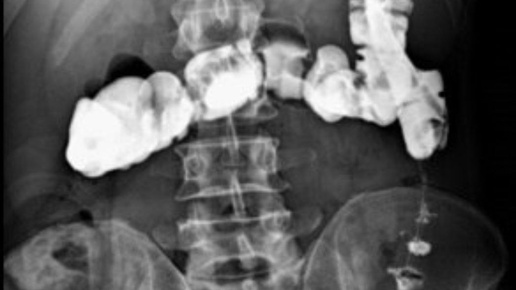

📌 Ирригоскопия/ирригография Многие молодые рентгенологи только слышали об ирригоскопии, но ни разу не проводили это исследование. Да и я за свою профессиональную деятельность не сделала и десятка ирригоскопий. 👩⚕ А ведь моя бабушка-рентгенолог, которой сейчас 91 год, каждый день на своем рабочем месте делала эти исследования. 🖥 Итак, давайте разберемся, что это за исследование такое. 👀 Что смотрим? При ирригоскопии проводяи исследование толстой кишки с ретроградным введением в нее рентгенконтрастного препарата (посредством клизмы)...